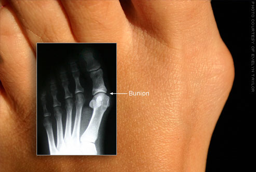

«Κότσι»

Το «κότσι», ή στην ιατρική ορολογία «Βλαισός μεγάλος δάκτυλος», είναι ένα οστεώδες εξόγκωμα στη βάση του μεγάλου δακτύλου που προκαλεί την μετατόπιση αυτού του δακτύλου προς τα υπόλοιπα. Με αυτό τον τρόπο χαλάει η ευθυγράμμιση των δακτύλων και προκαλείται πόνος λόγω της πίεσης ή λόγω αρθρίτιδας, ενώ επίσης μπορεί να δημιουργηθεί κάλλος. Οι τρόποι αντιμετώπισης περιλαμβάνουν παυσίπονα, ειδικά προστατευτικά επιθέματα, ειδική προσθήκη στα παπούτσια ακόμα και χειρουργική αντιμετώπιση σε κάποιες περιπτώσεις. Επίσης προτείνεται να επιλέγονται ευρύχωρα και άνετα παπούτσια και να αποφεύγονται τα ψηλά τακούνια.